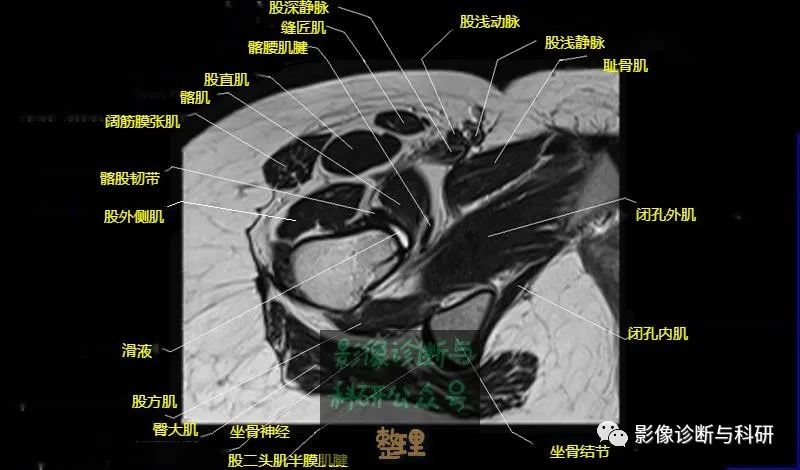

髋关节MR轴位详细标注